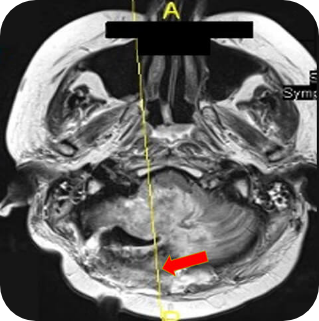

Fatima's repeat cerebral CT showed enlargement of

the mass and complete obliteration of the fourth

ventricle. Cerebellitis–encephalitis involving all of the

right (and a large portion of the left) cerebellar vermes

and the base of the right occipital lobe was also seen

Images supplied with permission of treating clinician.